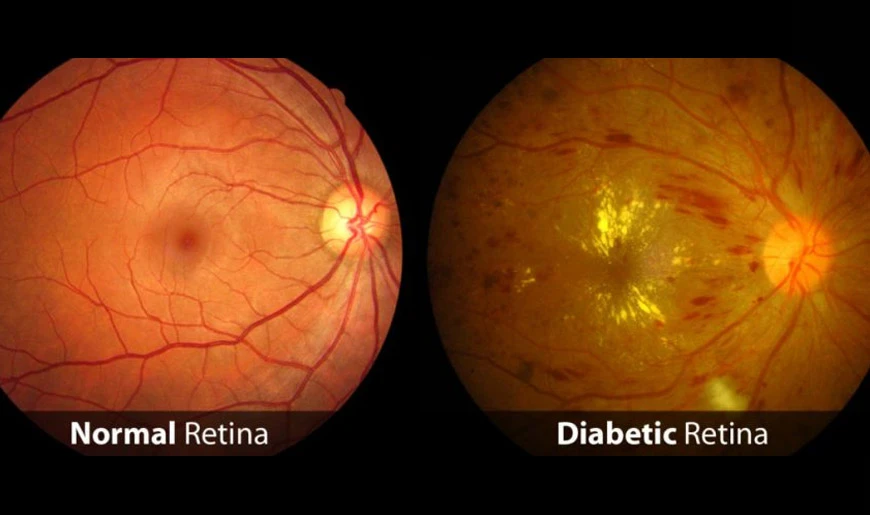

Diabetic retinopathy progresses in stages and may initially present without noticeable symptoms. Understanding these stages helps patients and caregivers recognize the importance of early treatment and regular eye exams:

1. Background (Non-Proliferative) Diabetic Retinopathy

At this stage, small blood vessels in the retina are damaged, but vision remains largely unaffected. Patients may have tiny hemorrhages or microaneurysms, but these often go unnoticed without a professional eye exam.

What are the causes of diabetic retinopathy?

Diabetic retinopathy is caused by damage to the small blood vessels in the retina, primarily due to prolonged high blood sugar levels. Over time, elevated glucose can weaken vessel walls, cause leaks, or block blood flow, depriving the retina of oxygen and nutrients. Risk factors include the duration of diabetes, poorly controlled blood sugar, high blood pressure, high cholesterol, smoking, and pregnancy. People with type 1 or type 2 diabetes are susceptible, and the likelihood increases with age. Proper management of blood sugar, blood pressure, and cholesterol can significantly reduce the risk of developing this eye condition.